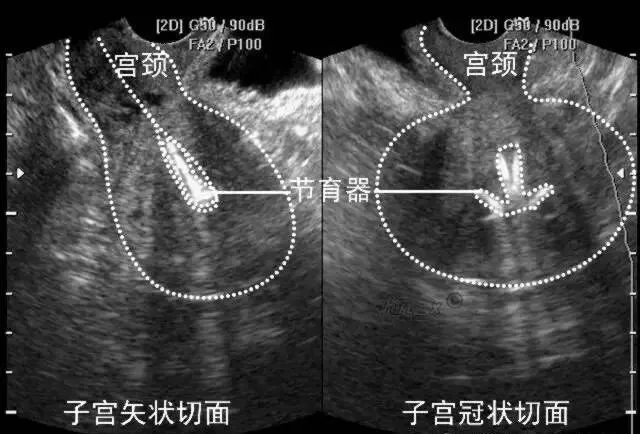

●声像图表现:宫腔内线性、圆形或三角形强回声。

●宫内节育器位置正常:节育器强回声位于宫腔中心,其周围内膜显示为低回声的晕圈。在子宫纵切面可判断宫内节育器在宫腔内的位置正常位置的宫内节育器应全部位于宫腔内,且节育器最下缘不低于宫颈内口。

宫内节育器位置异常声像图